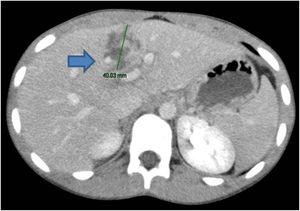

A 16-year-old male with an unremarkable past medical and surgical history suffered blunt abdominal trauma after a bicycle accident, in which the upper quadrants of the abdomen were injured by the handlebar. The patient did not lose consciousness. Upon arrival at the emergency department he was hemodynamically stable, and his physiologic parameters were within the normal range. Physical examination produced intense localized pain in the right hypochondrium and epigastrium. Laboratory study results were unaltered, with hemoglobin of 13.3 g/dl and hematocrit of 40.7%. An abdominal computed axial tomography scan identified hepatic lacerations at the level of segments IVa and IVb (Figs. 1 and 2), with no signs of active bleeding, corresponding to grade III injury, according to the organ injury scale of the American Association for the Surgery of Trauma (AAST),4 and moderate grade II injury, according to the World Society of Emergency Surgery (WSES) guidelines.5